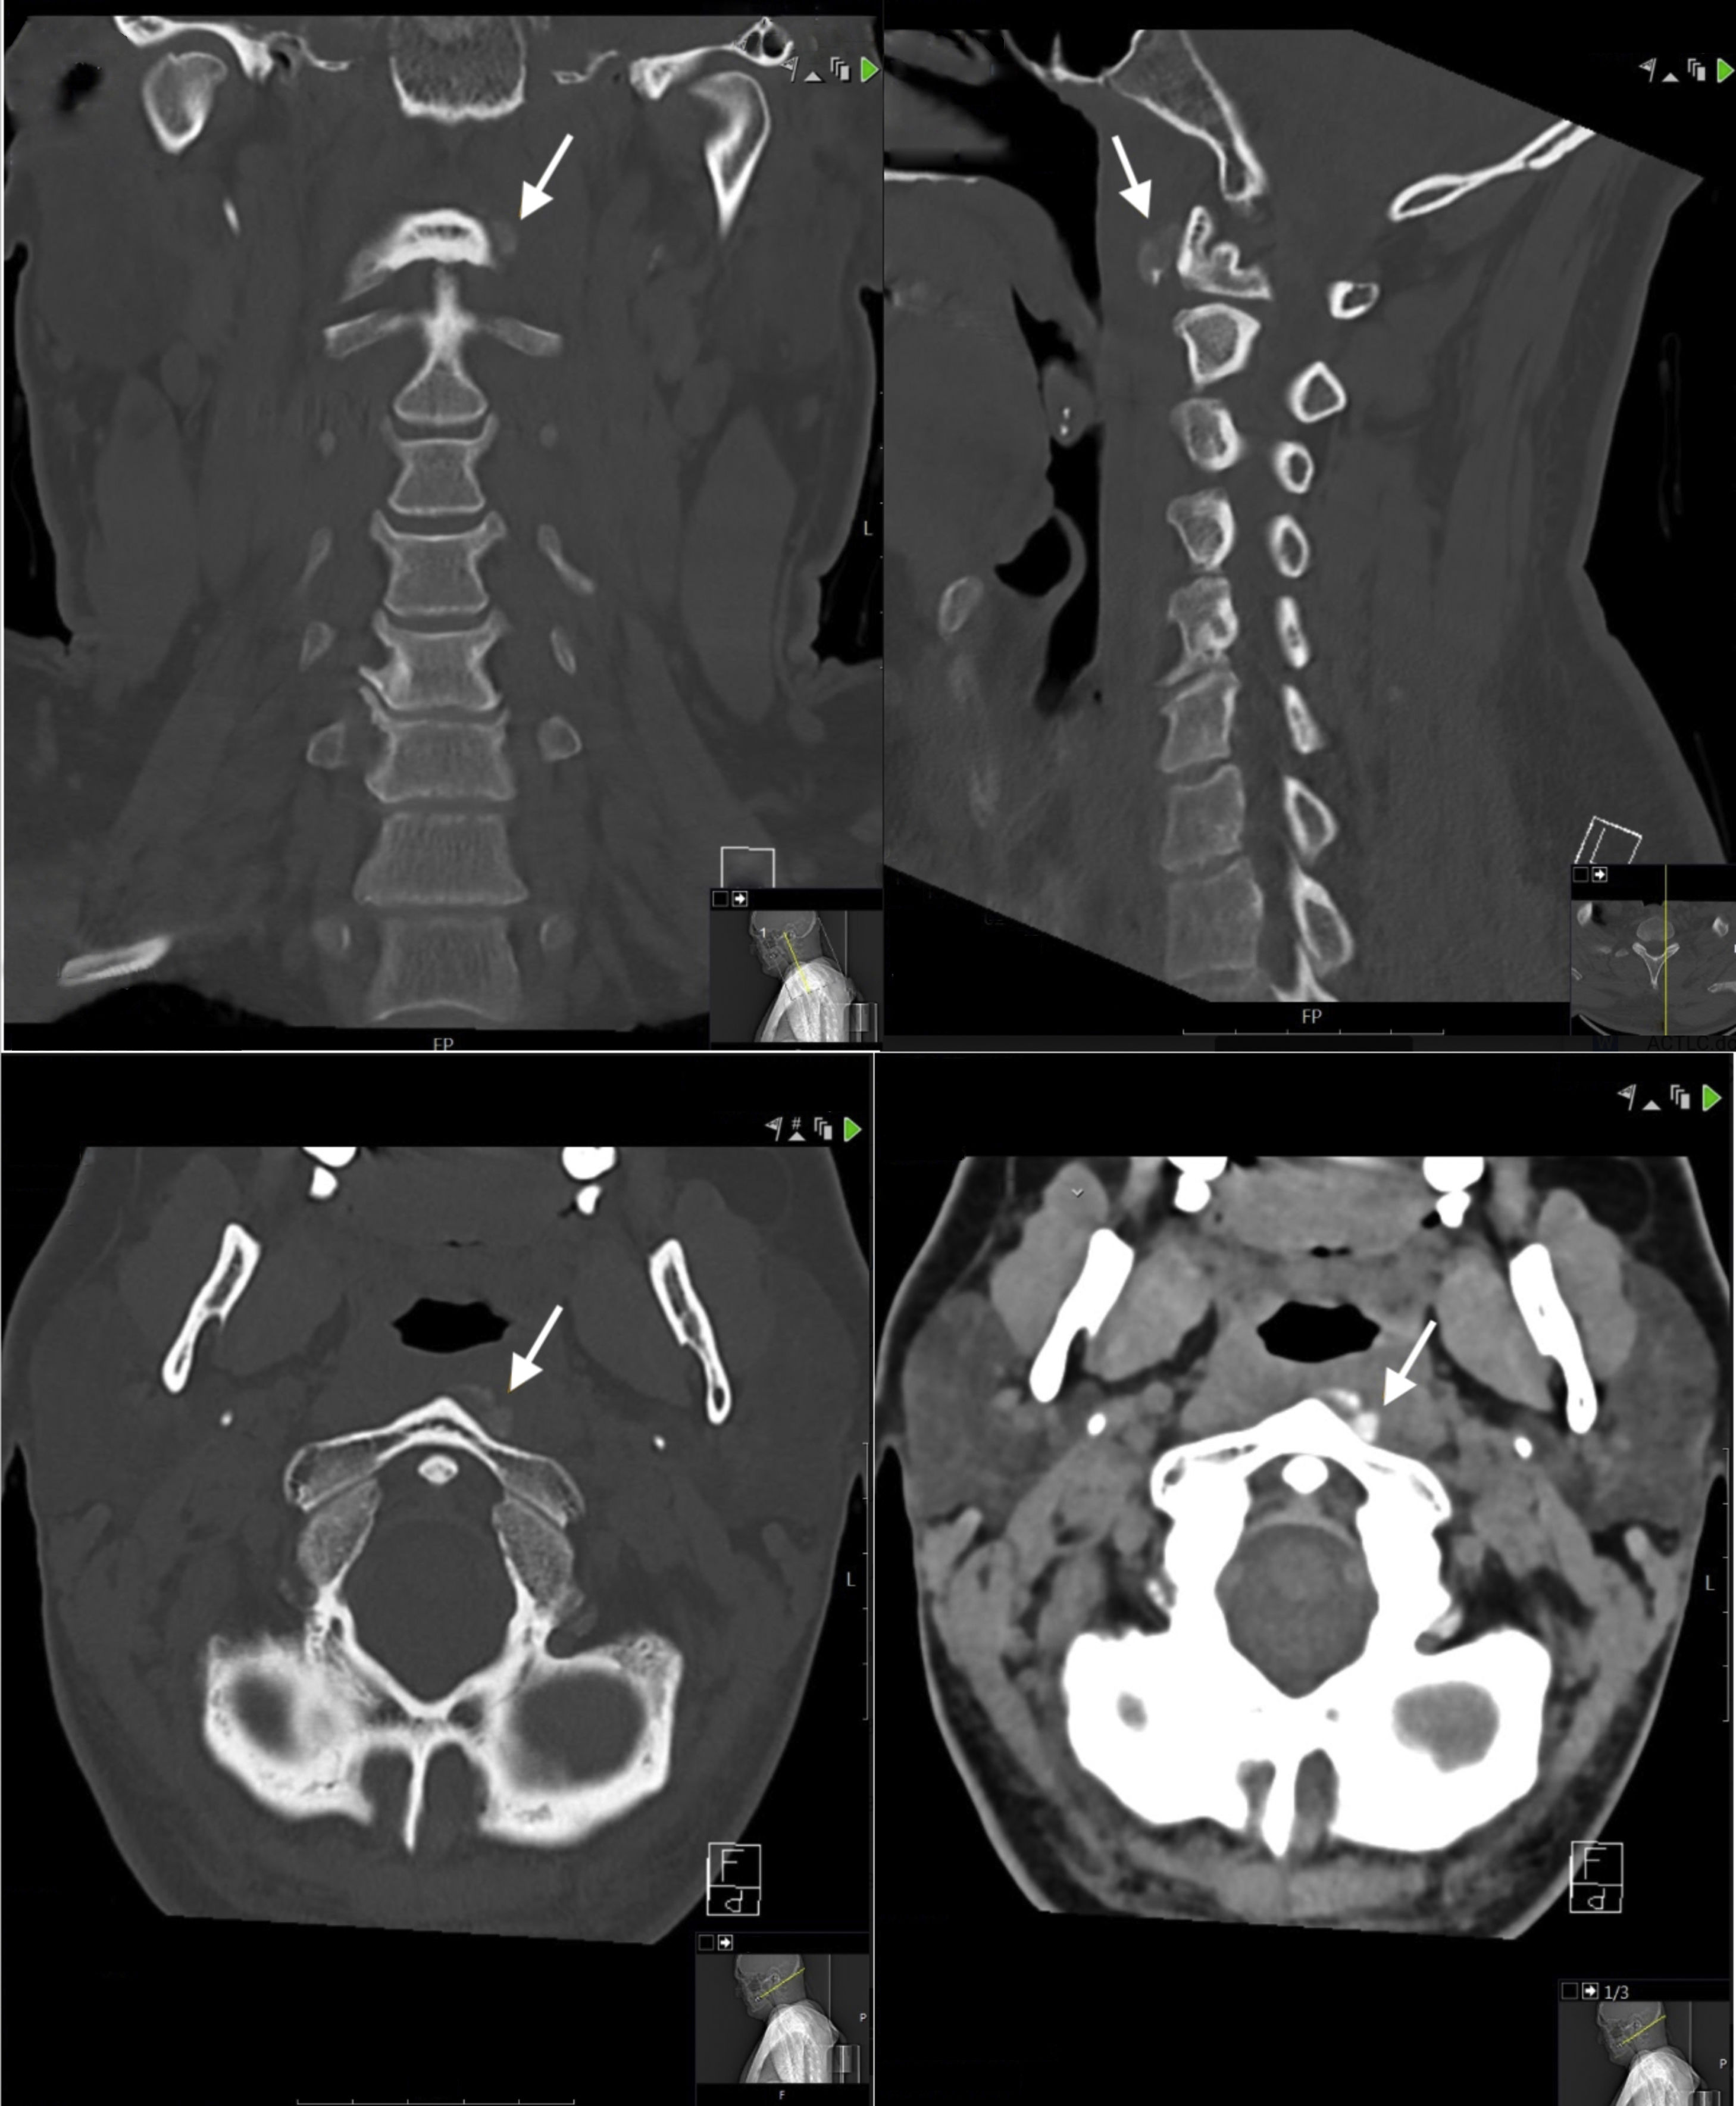

A 44-year-old man presented with a 7-day history of persistent significant neck pain, dysphagia and difficulty with swallowing. The patient reported having moved heavy stuff prior to the beginning of the symptoms. Throughout the last week he sought relief through painkillers, kinesitherapy and acupuncture, none of which yielded any help. Physical examination revealed no obvious swelling neither pus or fever. The patient did not show any findings of paraesthesia nor loss of strength in the arms. Neck flexion was slightly painless but extension and rotation to both sides was very limited. The patient did not have a history of musculoskeletal pain in other locations; therefore, any other potential site of soft tissue or intra-articular calcifications has not been investigated. Cervical CT revealed a soft tissue calcification anterior to C1–C2 vertebrae on the left side. Given the localization of the calcification and the patients symptoms a tentative diagnosis of acute calcific tendonitis of the longus colli (ACTLC) was made.

The first known cases of acute calcific longus colli tendinitis dates back to the 60s. Hartley7 claimed a relationship between the presence of prevertebral calcifications on conventional radiography and acute neck pain, odynophagia, and limited cervical ROM and Fahlgren et al.8 described an association between these calcifications and the superior tendon of the longus colli muscle. The confirmation of such an association, however, would only come many years later, in 1994, by Ring et al. who demonstrated the presence of hydroxyapatite crystal deposition in this particular disorder.9 Following this achievement, the literature has observed a growing tendency in the published reportsver over ACTLC with over 100 papers to date, with the majority appearing in radiology and neuroradiology journals. Of note, only around 10 of these papers have been published in rheumatology journals. Almost all of these papers reported neck pain and limitation of range of motion as the primary complaints of patients. Importantly, more than 1 of every 10 patients received useless antibiotherapy, demonstrating the importance of including ACTLC as a differential in neck pain. In almost 90% of cases NSAIDs provided comfort in symptoms within an average of 2 weeks. The disease is, indeed, accepted to be a self-limiting condition with a treatment duration of an average of 2 weeks. In our specific case, the diagnosis was made using a CT scan and the patient was prescribed NSAID treatment for 10 days, after which he reported complete resolution of symptoms (Fig. 1).